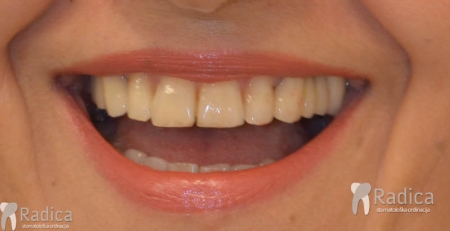

U ovom slučaju je 41.godinu starom pacijentu počeo nicati impaktirani desni gornji očnjak pri čemu je ugrozio lateralni sjekutić. Pacijentu je stavljen fiksni aparat te je zub smješten u luk. Kako je pacijent odustao od postave aparata u donjoj čeljusti na kraju nije dobivena zadovoljavajuća okluzija na što je upozoren.